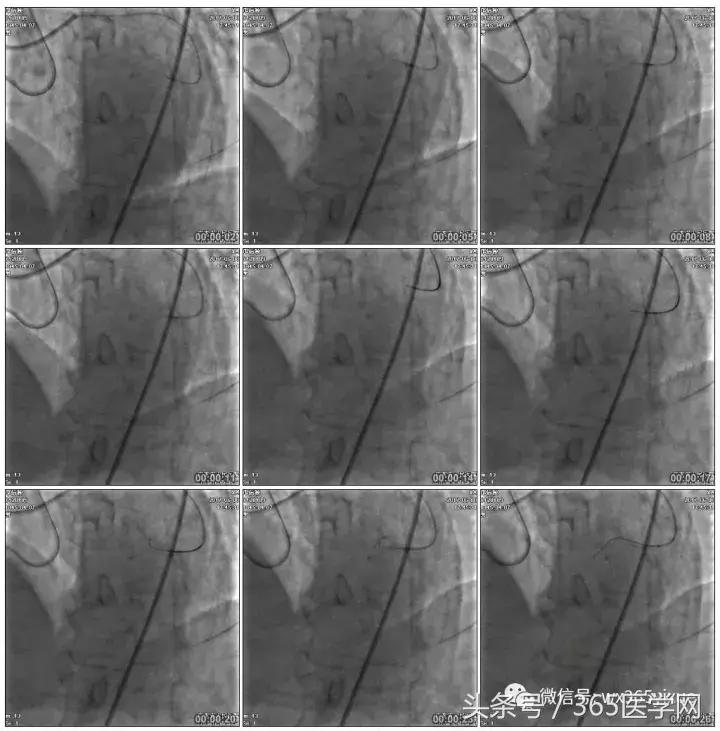

正向130cmFinecross微导管支持下尝试送PILOT150、Gaia 2导丝无法通过RCA闭塞段

SION导丝通过侧枝

逆向导丝:更换Gaia2

正向导丝:Gaia2,PILT150

正向导丝knuckle

2.5*15mm球囊扩张,逆向导丝尝试,但未能进入正向GC

1.正向2.5*15mm球囊扩张,Reverse CART

2.Guidezilla延长导管辅助下,逆向导丝进入正向GC